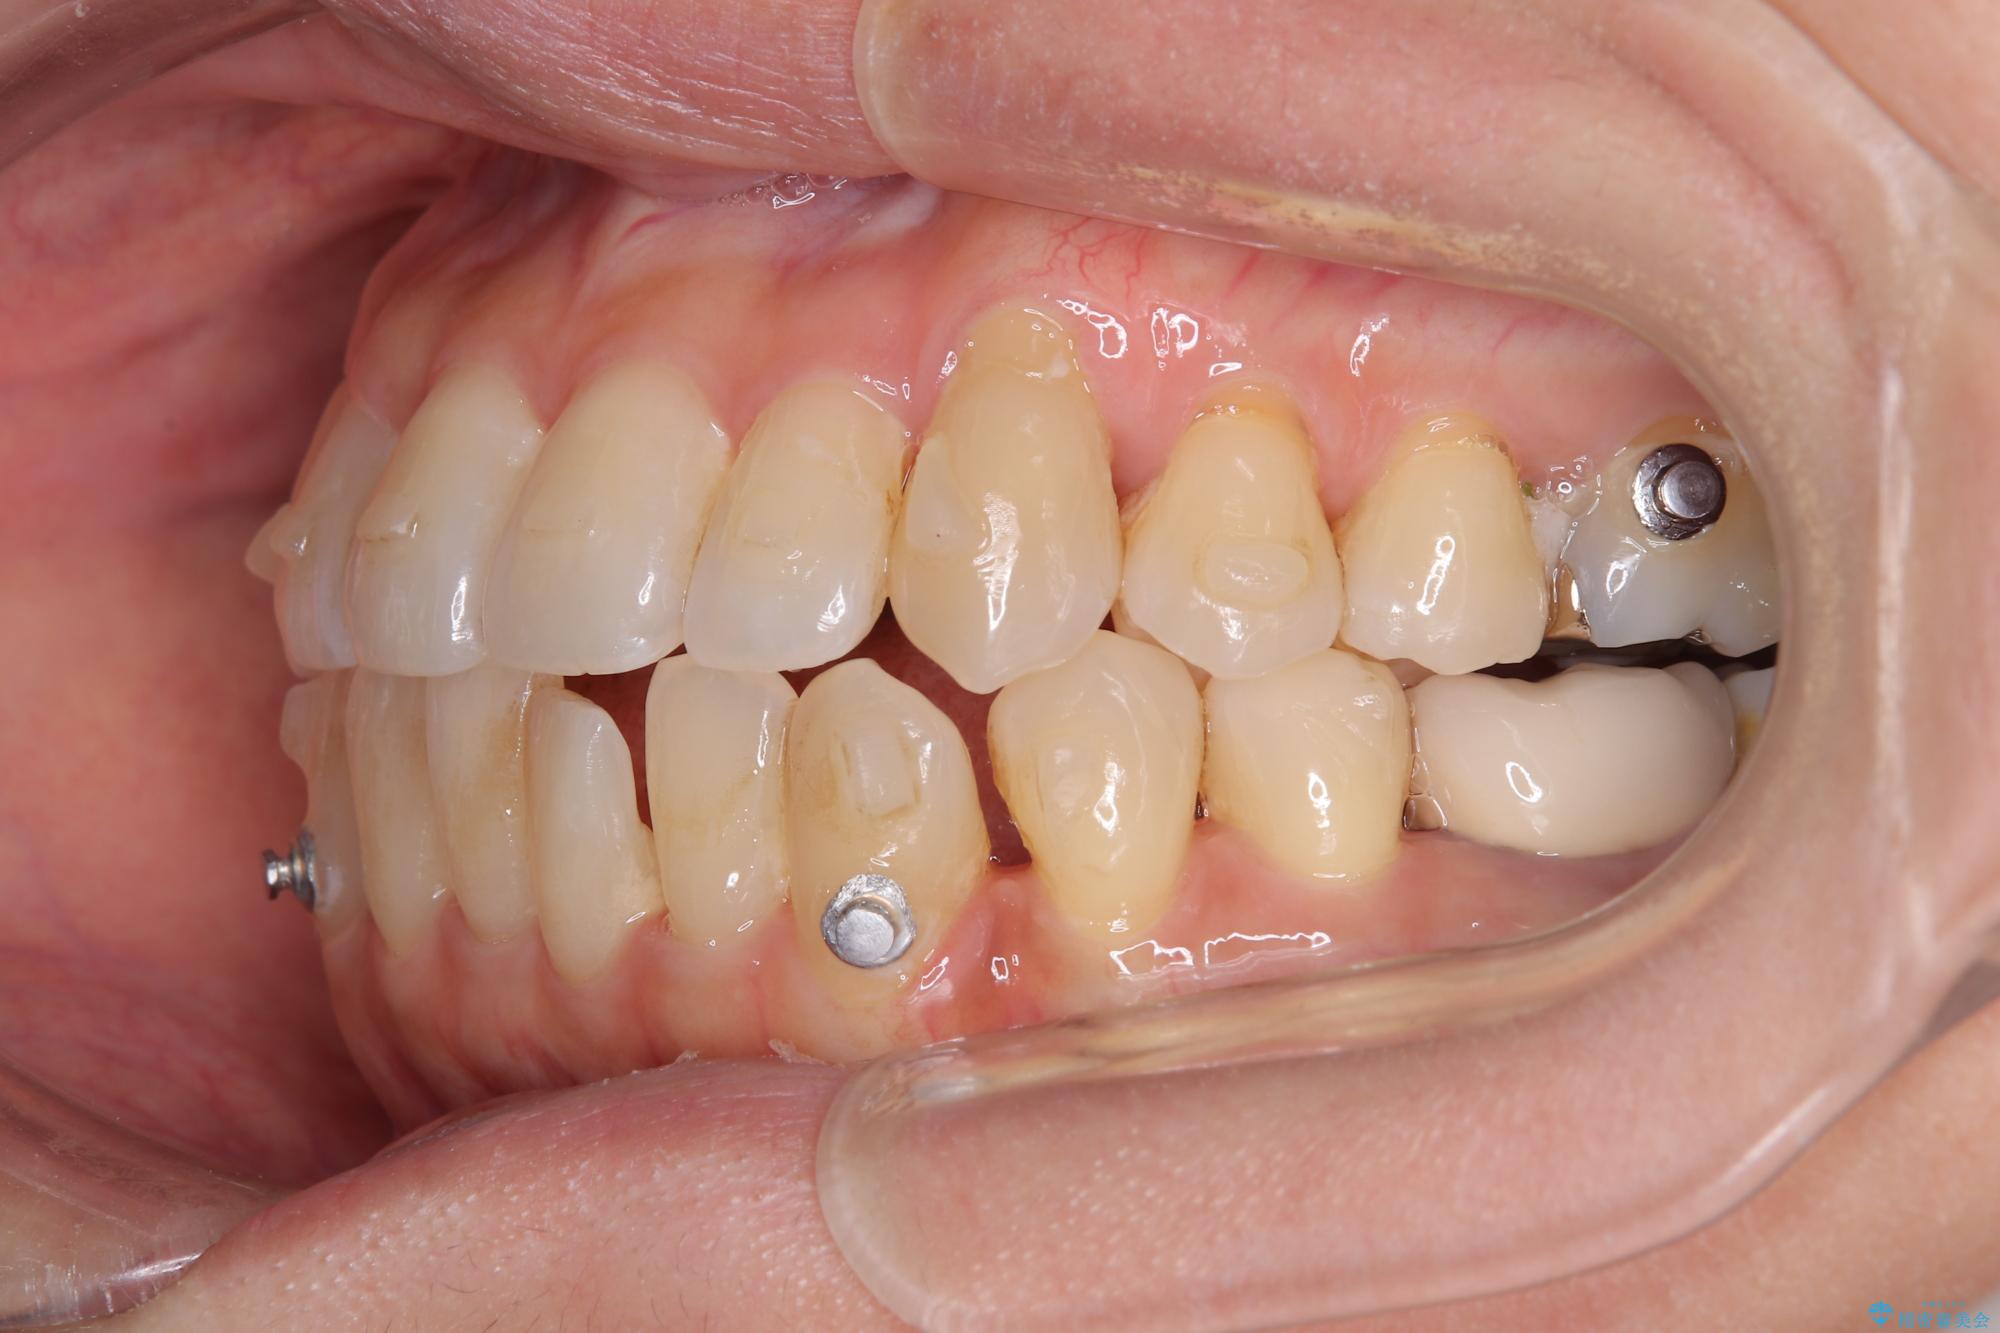

受け口傾向の骨格であり、前歯はクロスバイトまたは切端咬合となっており、下顎を中心に歯列全体の後方移動を行い、IPR(歯と歯の間を削る)によってデコボコが解消するように設計し、インビザラインにより治療を行うこととしました。

受け口傾向のインビザライン矯正は比較的治療を行いやすいため、きれいに仕上げることができました。舌の突出癖が顕著であったため、改善のためのトレーニングをしっかりと行っていただきました。